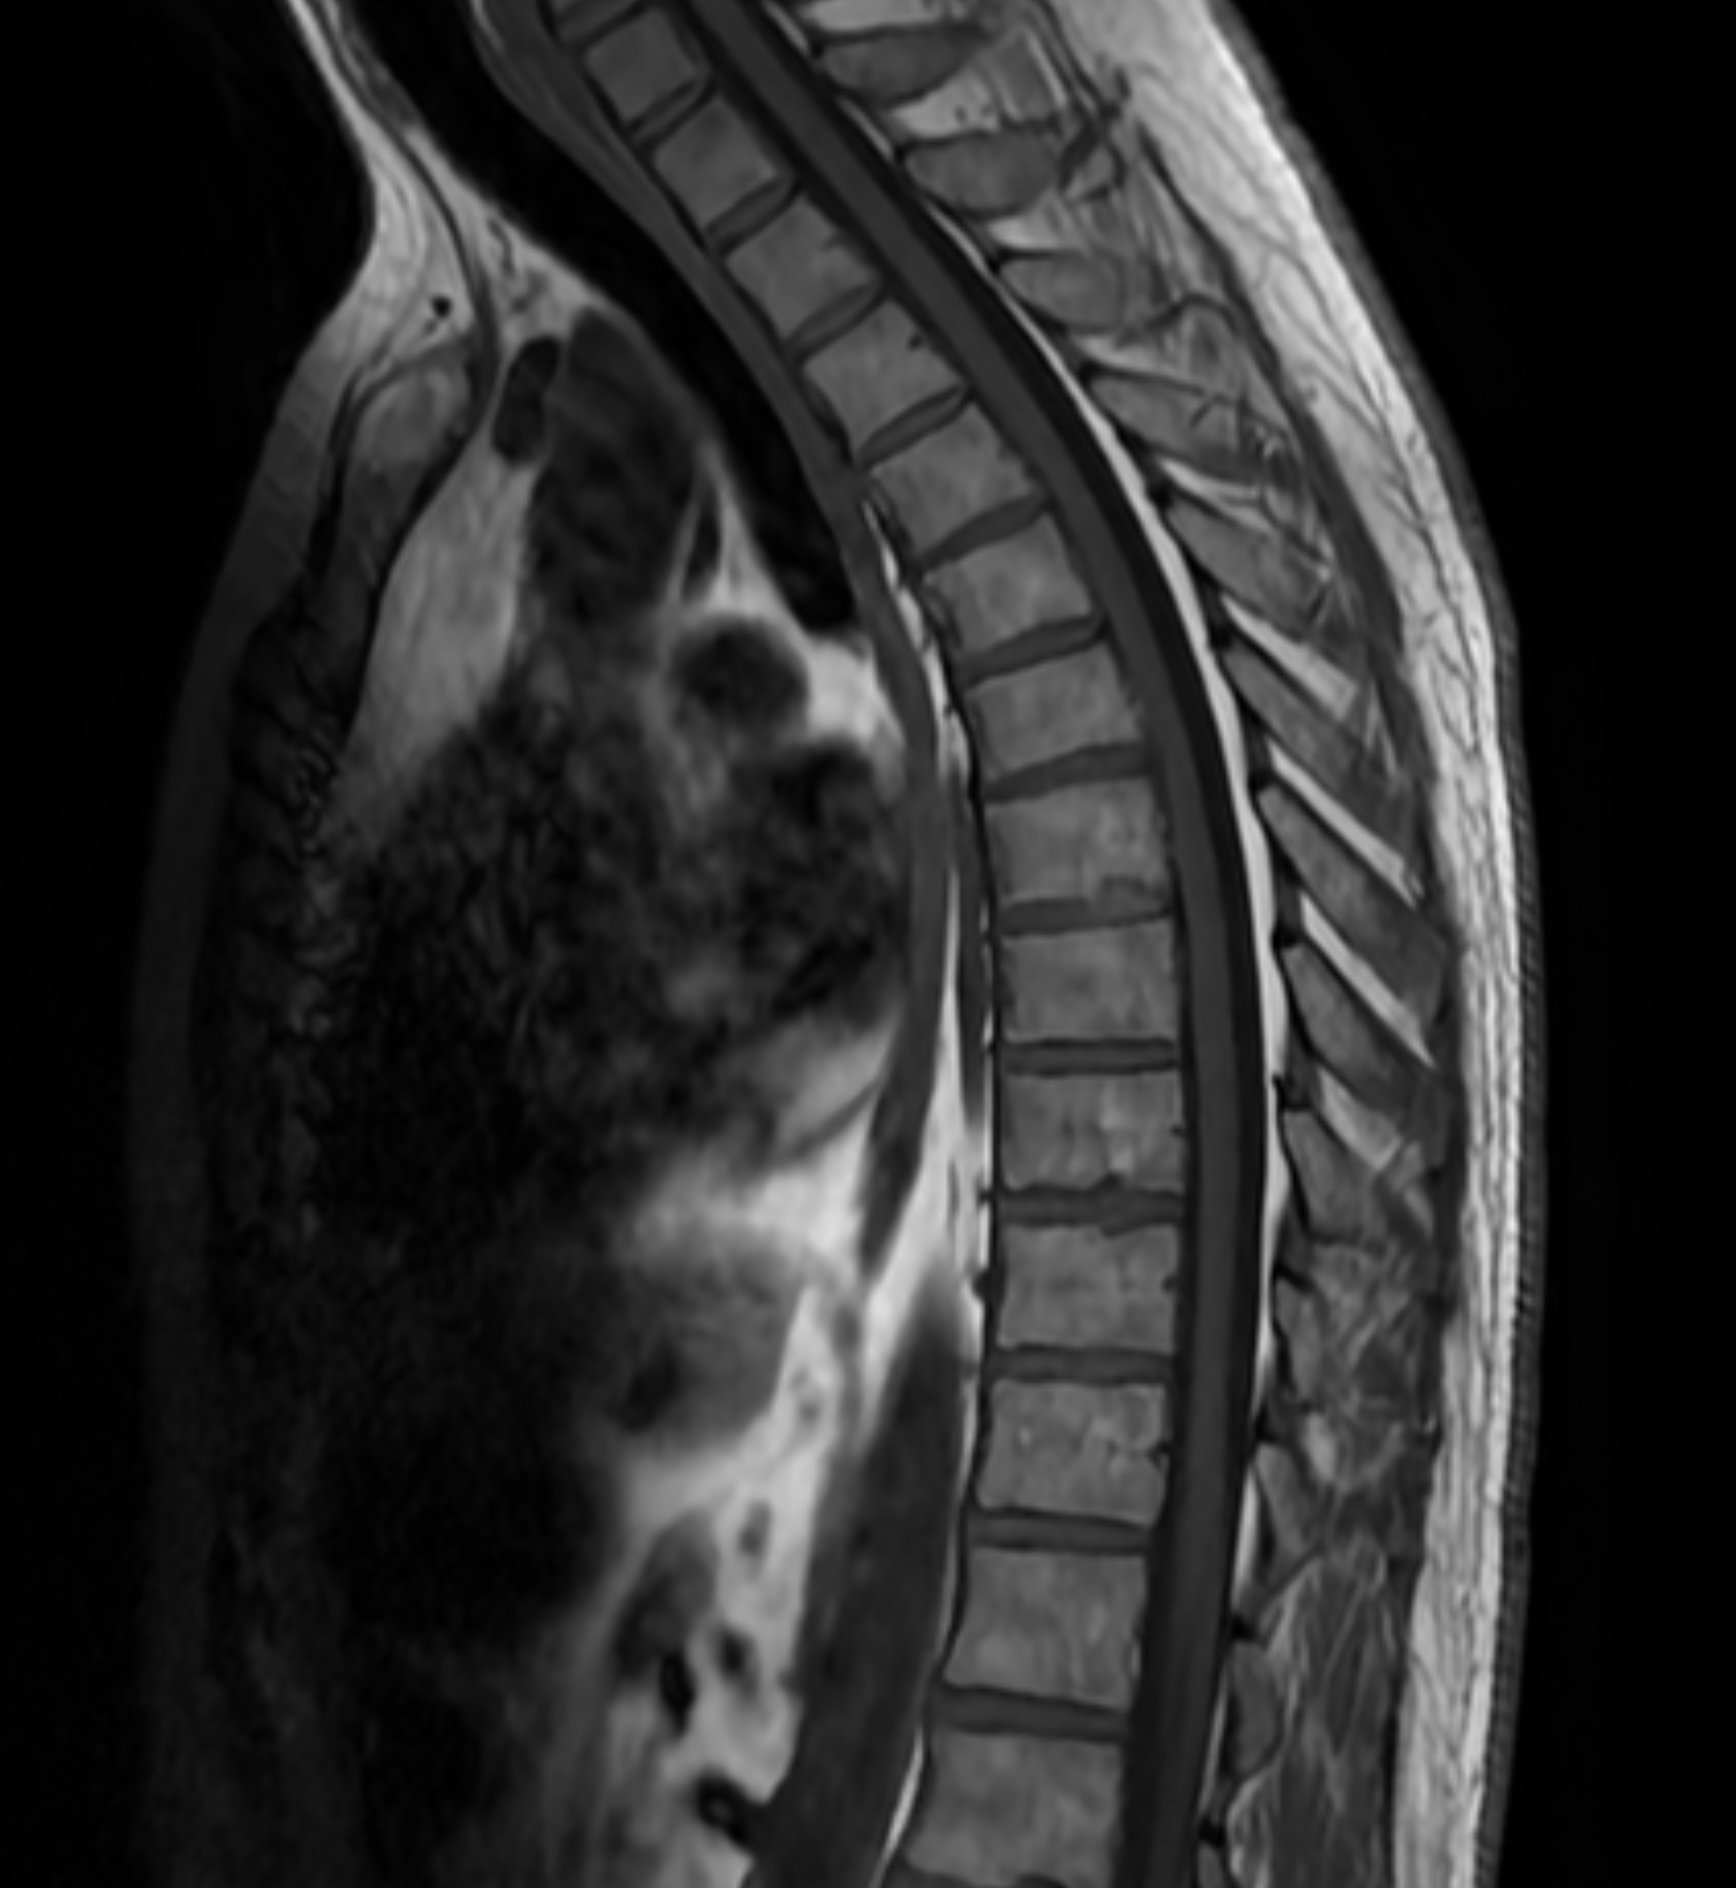

MR Helrygg är en avancerad magnetkameraundersökning som omfattar hela ryggraden, från halsrygg (cervikal) och bröstrygg (thorakal) till ländrygg (lumbal). Undersökningen ger en detaljerad bild av samtliga delar av ryggraden och omgivande strukturer, vilket gör det möjligt att identifiera både akuta och kroniska förändringar. Eftersom undersökningen täcker alla ryggsegment rekommenderas den framför allt för dig som har mer omfattande eller diffusa besvär som inte kan lokaliseras till en specifik del av ryggen.

Magnetkameraundersökningen är helt strålningsfri, smärtfri och ger högupplösta bilder med millimeterprecision. Remissen skickas direkt och du får ett tydligt skriftligt utlåtande av en erfaren röntgenläkare baserat på resultaten.

Vilka sjukdomar och förändringar kan upptäckas vid MR helrygg?

MR Helrygg kan identifiera ett brett spektrum av sjukdomar och förändringar i ryggraden. Undersökningen ger en detaljerad bild av alla ryggsegment och kan bland annat påvisa:

- Diskförändringar: Diskbråck, buktande diskar och degenerativa förändringar.

- Förträngningar: Spinal stenos samt annan trängsel kring ryggmärg och nervrötter.

- Ledsjukdomar: Artros och inflammatoriska förändringar i facettlederna.

- Skeletala förändringar: Skolios, skelettdestruktioner och spinal skleros.

- Nervpåverkan: Tecken på tryck eller irritation av nervrötter, exempelvis vid ischias.

- Tumörer och metastaser: Primära tumörer, metastaser och andra vävnadsförändringar.

- Inflammatoriska och neurologiska förändringar: Multipel skleros (MS-plack), Bechterews sjukdom och andra inflammatoriska processer.